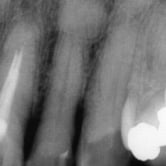

Granuloma Periapical

Un granuloma periapical es una pequeña masa de tejido inflamatorio en la punta de la raíz del diente, generalmente como respuesta a una infección crónica.

Los pacientes pueden no sentir dolor, pero el área puede estar sensible al tacto.

El tratamiento de conducto es necesario para eliminar la fuente de la infección y permitir la curación del tejido.